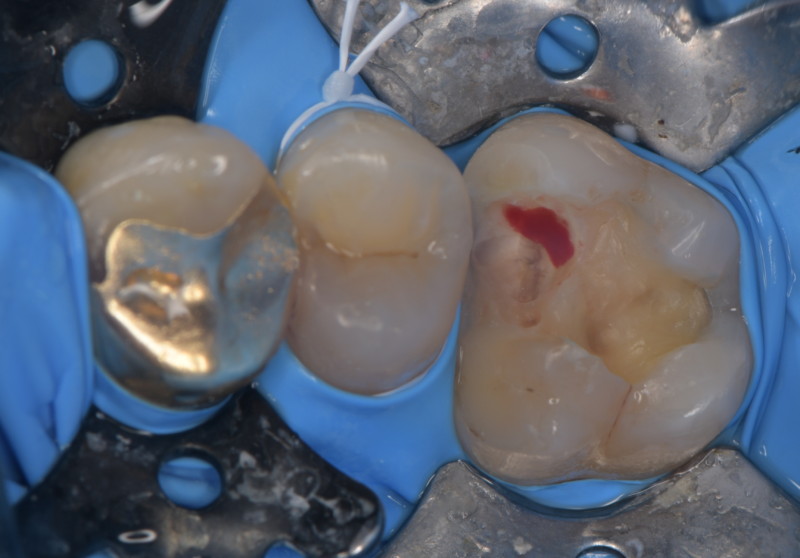

患者さんは歯がとても沁みると訴える歯医者さんでした。適切な治療を受け、セルフケアやメンテナンスを完璧にしているはずの歯医者さんでも虫歯になる事があります。 その原因は噛み合わせや生活習慣です。負荷の大きな力から歯のひび割れ(マイクロクラック)が起こり、その間を伝って細菌に栄養が運ばれ、知らないうちに進行してしまいます。 顕微鏡を使い、ひび割れを取っていきます。このひび割れが残っていると再び、細菌の感染経路となるため、可能な限りとります。これは十分な治療時間と顕微鏡がなければ不可能な仕事です。   虫歯を取っていくと神経の露出が見られました。 MTAセメントにて神経保存を行いました。 だんだんと、症状が改善してきたそうなので、今後、最終修復を行う予定です。       リスク 極端に硬いものを噛むと取れたり、かける可能性があります。 ラバーダム、顕微鏡等を使用し適正な時間を確保された治療は自由診療となります。 各種治療費はこちらから